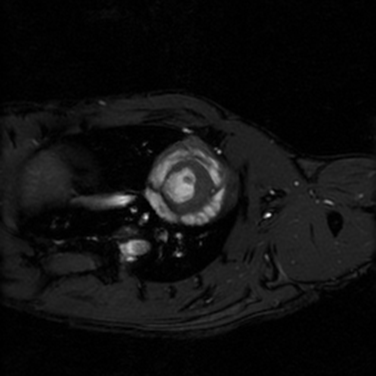

Boğaziçi Üniversitesi Hedefli Tedavi Teknolojileri Merkezi (Boğaziçi CT3) Deney Hayvanları Görüntüleme Birimi, Türkiye’nin ilk preklinik (deney hayvanlarında kullanım için özelleşmiş) 7T MRG (manyetik rezonans görüntüleme) cihazının yanı sıra preklinik BT (bilgisayarlı tomografi) ve hem MRG hem de BT tarayıcıları ile entegre edilerek PET-MRG ve PET-BT çalışmalarına olanak tanıyan PET tarayıcısı ile araştırmacılara ve sektördeki kuruluşlara eşsiz bir altyapı sunmaktadır.

Birimimizde; tüm vücut ve bölgesel MR taramaları, doku karakterizasyonu, metabolik görüntüleme, moleküler hedeflerin izlenmesi ve farmakokinetik değerlendirmeler gerçekleştirilebilmektedir. Ayrıca hayvan kabul ve karantina alanlarımız, uluslararası etik standartlara uygun olarak yapılandırılmıştır.

Yüksek alan kuvveti sayesinde sağlanan üstün görüntü kalitesi ve hassasiyet, özellikle onkoloji, nörobilim, kardiyovasküler ve farmasötik araştırmalarda büyük avantajlar sağlamaktadır. Araştırmalarınıza özgü deneysel protokoller geliştirme, planlama ve analiz süreçlerinde, deneyimli teknik ekibimizle kapsamlı destek sunuyoruz.